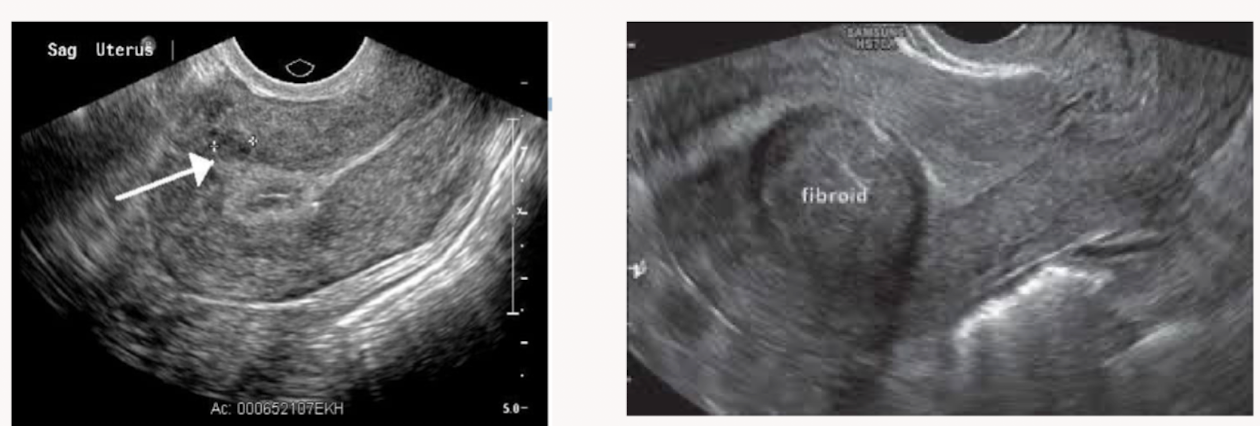

Which patient is likely to have fertility problems?

Patient on the right because the fibroid is larger and more centrally located (pushing into the endometrium)